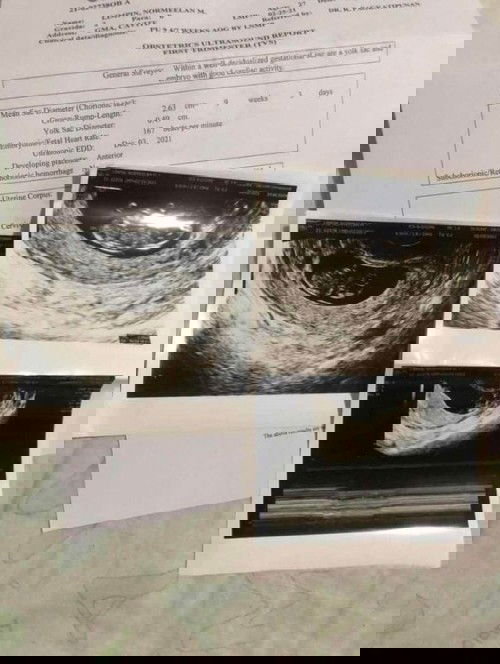

9 weeks 3days Preggy

Trans V result. Bukas ko palang po makakausap OB ko kasi bukas palang schedule ko. Okay po ba ung result ko? #pregnancy

yes po. normal. congrats 😍